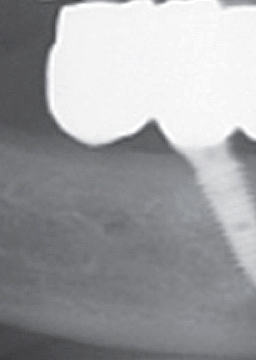

풀아치임플란트 시술이란 상악 하악에 각각 4개에서 6개까지 인공 치근을 심어 잇몸뼈에 심은 후에 하나로 연결된 보철물을 임플란트에 고정하는 시술을 말하였어요. 이러한 풀아치 임플란트 치료는 발치부터 임플란트 시술, 보철물 장착까지 전 과정을 3D CT와 같은 디지털 시스템에 기반하다 보니 무절개 수술이 가능할 수 있었어요. 이러한 풀아치임플란트 시술은 기존 임플란트에 비하여 식립 개수가 절반 정도이다 보니 경제적인 부담이 줄어들 수 있었어요.

또한 뼈 이식 없이 남아 있는 건강한 잇몸 뼈를 이용하여 수술이 가능해지며, 이로 인하여 잃어버렸던 저작기능을 회복할 수 있기에 기능적인 측면에서도 큰 기대효과를 볼 수 있었어요. 게다가 인공치근 개수가 적다 보니 잇몸 절개로 인해 발생된 출혈을 줄일 수 있었으며, 수술 시간 및 회복 기간이 짧다 보니 전체적인 치료 기간이 일반 임플란트 치료에 비하여 짧을 수 있었어요.

이렇게 반포치과에서는 편안한 치료 과정을 거치다 보니 수술 당일에 귀가가 가능해질 수 있었으며, 탈부착으로 번거로웠던 틀니로부터 해방이 가능해질 수 있었어요. 게다가 회복 기간이 빠르다 보니 일상생활으로부터의 복귀가 바로 가능해질 수 있었어요.